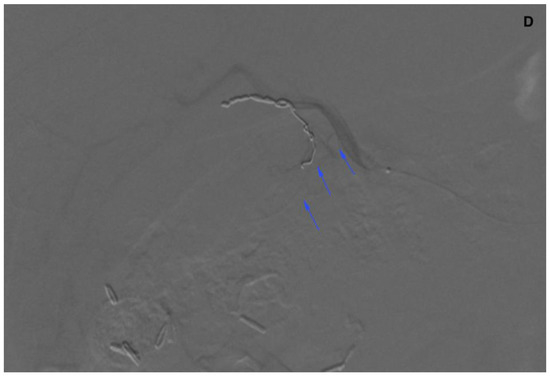

3.3. Abdominal Wall

There were three leaks through falciform arteries to the abdominal wall in 99mTc-MAA SPECT/CT. In two cases, dyna-CT confirmed their presence (Figure 5). In one case, there was no sign of contrast enhancement in the abdominal wall. These patients were not given SIRT.

Figure 6.

(A) Angiogram of the left hepatic artery showing falciform artery travelling medially beyond the margin of the liver. (B) Its presence was confirmed on Dyna-CT and showed contrast enhancement of the abdominal wall (arrows) (C), and on SPECT/CT after 99mTc-MAA injection (D) (crosshairs).